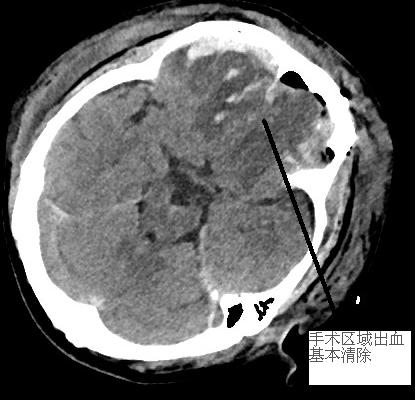

患者黃先生,在家中上衛(wèi)生間時不慎摔倒,受傷后出現(xiàn)昏睡情況,一開始家屬以為是小事,并沒有上心。后來,發(fā)現(xiàn)黃先生持續(xù)昏睡,怎么叫都沒有應答,且偶有躁動現(xiàn)象,并出現(xiàn)大小便失禁、發(fā)熱等情況,意識到病情嚴重,立即送至我院。經(jīng)急診CT檢查,提示黃先生雙側(cè)額顳葉多發(fā)腦挫裂傷伴腦內(nèi)血腫,額部硬膜外血腫,額部、左顳部及大腦鐮前部硬膜下血腫,創(chuàng)傷性蛛網(wǎng)膜下腔出血,額骨骨折,出血量較大,雙側(cè)額顳葉多發(fā)腦挫裂傷伴腦內(nèi)血腫臨近腦干(生命中樞),環(huán)池部分變窄,若病情再繼續(xù)惡化,將造成腦干功能受損,甚至影響呼吸、心跳,符合開顱手術指征。在征得家屬知情同意后,神經(jīng)外科團隊立即與前來本院查房的福醫(yī)大附二院黃金鐘主任就黃先生病情進行深入研討,制定手術方案,同時完善術前各項準備工作后,立即進入手術室緊急開顱手術。手術過程中,予以清除血腫,腦組織壓力減低,腦血管搏動有力。術后復查CT,手術區(qū)域血腫基本清除,環(huán)池受壓緩解,患者生命征平穩(wěn)。隨后進行后續(xù)康復治療。